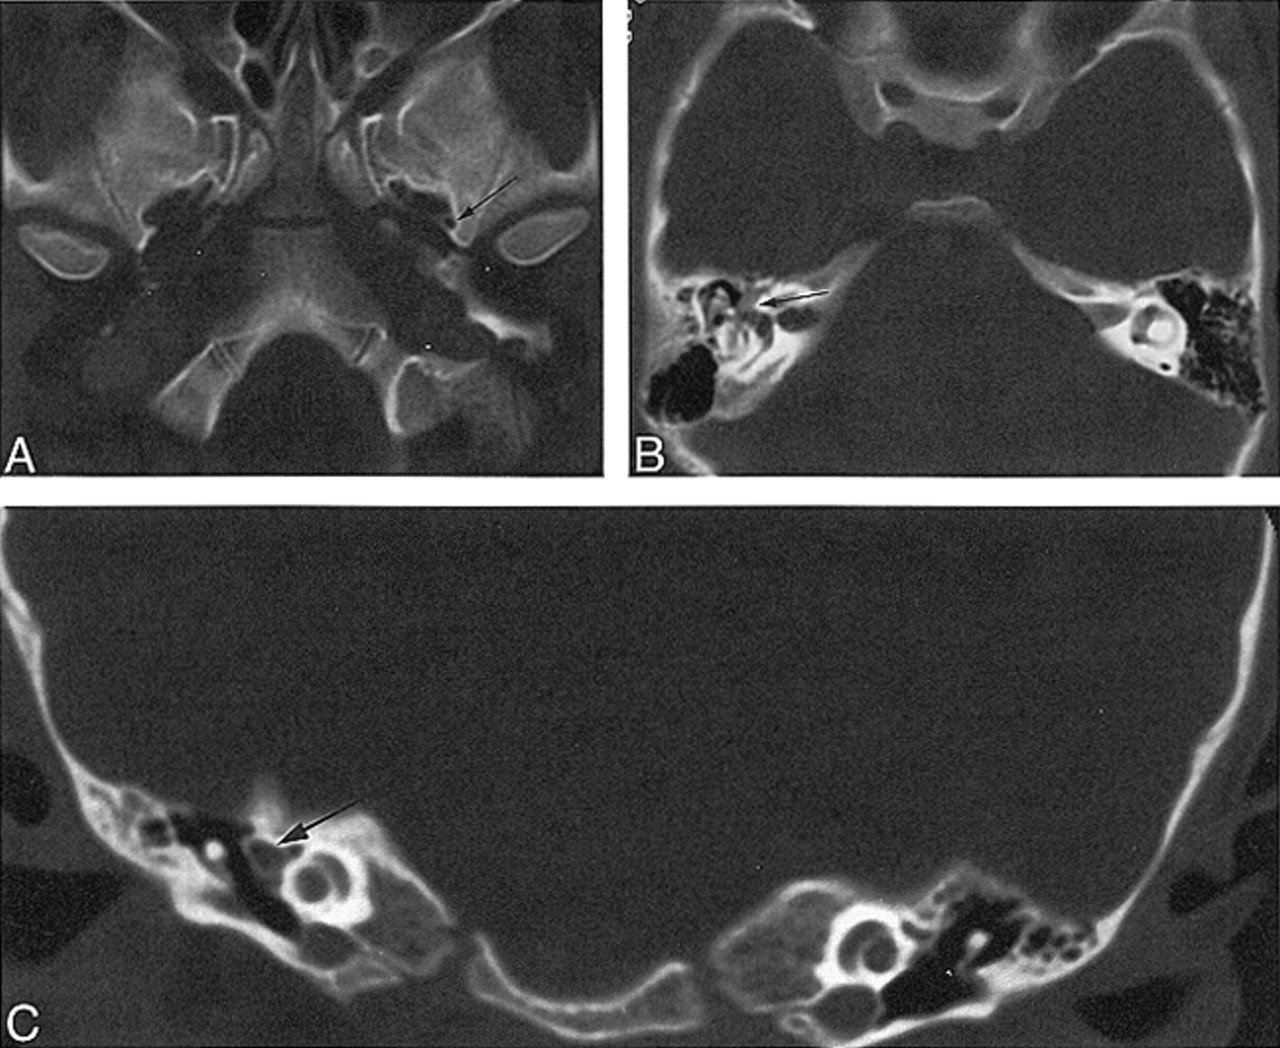

Case 3: 6-year-old girl with vertigo.

A, Axial CT scan shows a normal left foramen spinosum (arrow) and absence of the right foramen spinosum.

B, Axial CT scan through middle ear shows prominent soft tissue, representing facial nerve and PSA (arrow).

C, Coronal CT scan through middle ear shows prominent soft tissue, representing facial nerve and PSA (arrow).